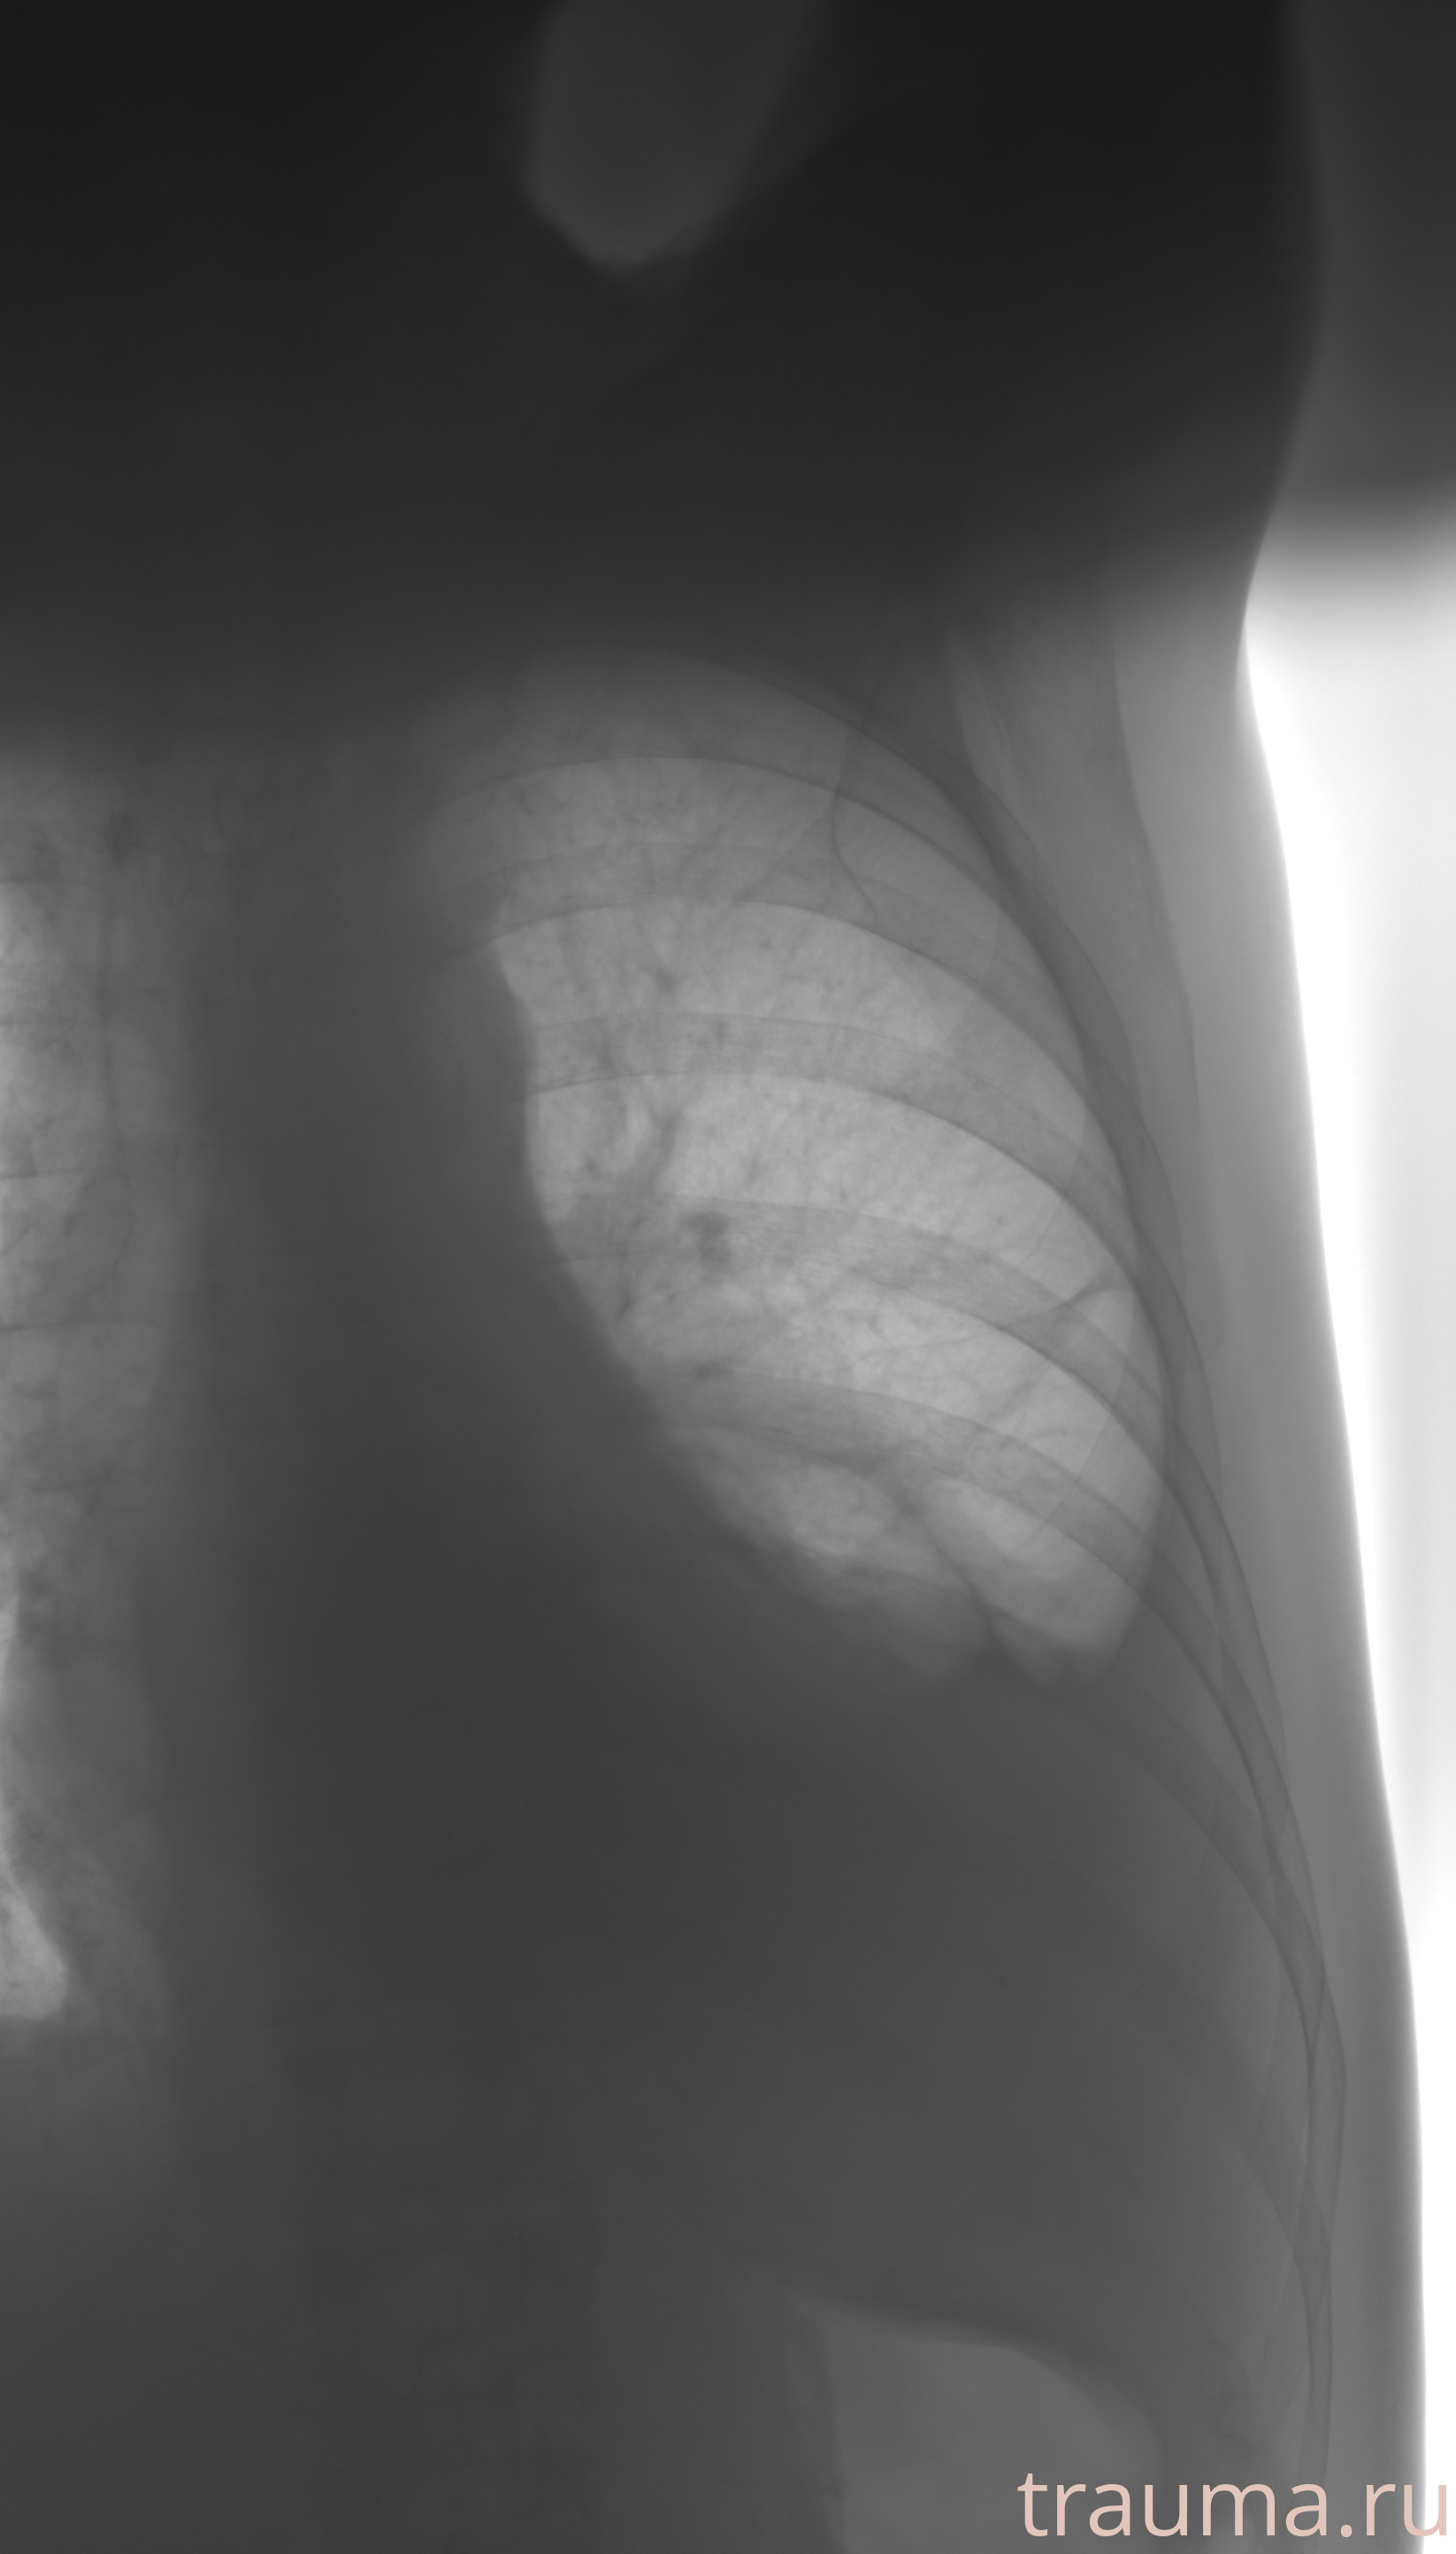

Рентгенограммы

Рентген на дому: по вашему адресу приезжает врач-рентгенолог, травматолог-ортопед с мобильным рентгеновским аппаратом, проводит диагностику травмы или заболевания, делает необходимые рентгенограммы, дает рекомендации по дальнейшему лечению. Получить качественные снимки в домашних условиях возможно благодаря уникальной методике, разработанной МосРентген Центром для института  Склифосовского